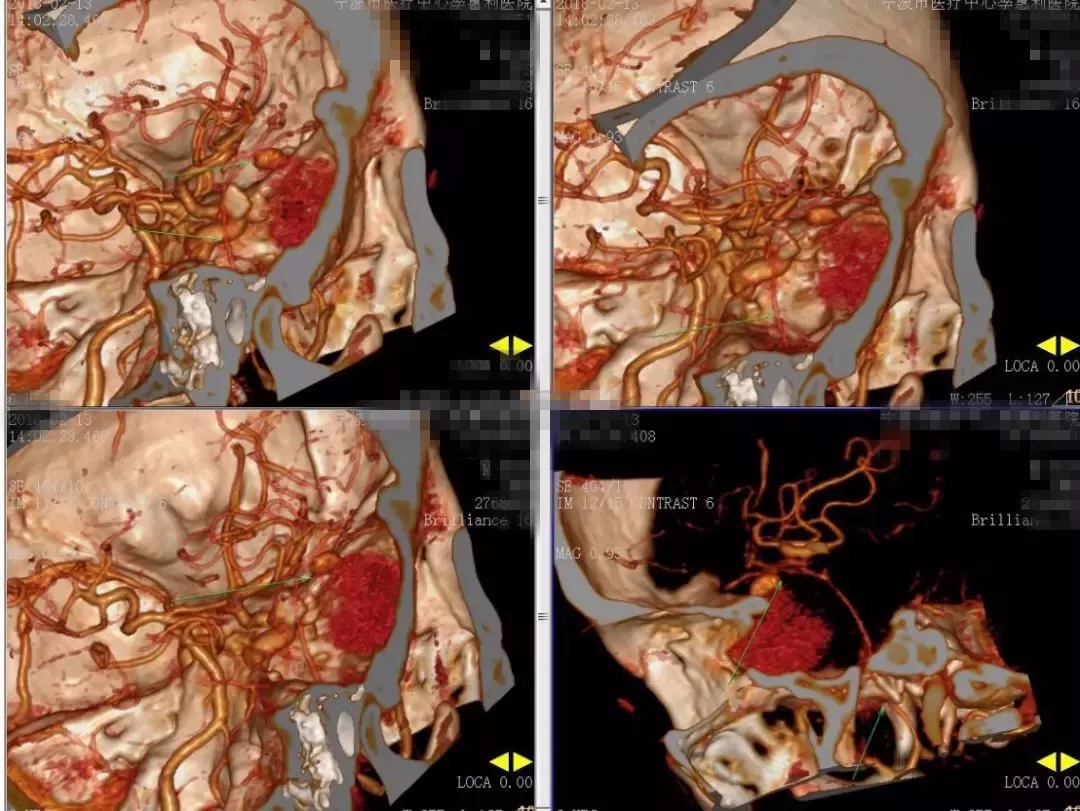

2018-2-13 CTA提示右颞部DAVF可能(图6),建议DSA。仔细阅片CTA未见明显引流静脉,考虑右侧脑膜中动脉假性动脉瘤可能更大。次日行 DSA检查,证实为“右侧脑膜中动脉假性动脉瘤”(图7)。当日即行“右侧翼点入路,脑膜中动脉假性动脉瘤切除加血肿清除术”(图8)。病理回报:镜下纤维细胞增生,可见血凝块伴机化(图9)。2018-2-27 复查CTA提示右侧脑膜中动脉假性动脉瘤术后改变,未见残余及复发(图10)。

图6. 2018-2-13 CTA提示右颞部DAVF可能。

图7. 2018-2-14 DSA提示右侧脑膜中动脉假性动脉瘤。